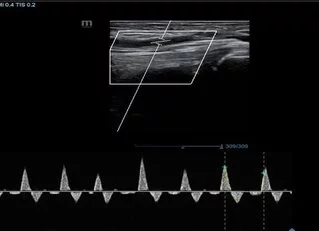

Doppler arterial de miembros inferiores

¿En qué consiste el Eco doppler arterial?

El equipo de ecografía funciona enviando sonidos a los vasos sanguíneos y posteriormente realiza una reconstrucción del interior del mismo.

El Doppler permite ver la anatomía de las arterias y saber cuales están obstruidas y cuales están sanas.

Durante el examen el equipo se pasa a lo largo de todo el trayectos de las arterias a estudiar.